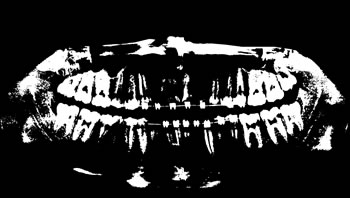

To thoroughly benchmark the methods studied here, the 1,500 images were distributed among 10 categories. The images were named, using whole numbers, in sequential order by category, aiming at not identifying the patients in the study. The process of categorizing the images was performed manually, selecting images individually, counting tooth by tooth, as well as verifying structural characteristics of the teeth. The images were classified according to the variety of structural characteristics of the teeth (see Table 5). Finally, the images were cut out to disregard non-relevant information (white border around the images and part of the spine) generated by the orthopantomograph device. After the clipping process, there was a change in the size of the images to 1991 ×\times 1127 pixels, but without affecting the objects of interest (teeth), as shown in Figure 2. The cropped images were saved on the new dimension to be used in the following stages, which will be presented in the next sections. Figure 3 shows an X-ray image corresponding to each of the categories of our data set.

Refer to caption

Figure 3: Examples of images from the data set categories of present work: (a) Category 1; (b) Category 2; (c) Category 3; (d) Category 4; (e) Category 5; (f) Category 6; (g) Category 7; (h) Category 8; (i) Category 9; (j) Category 10.